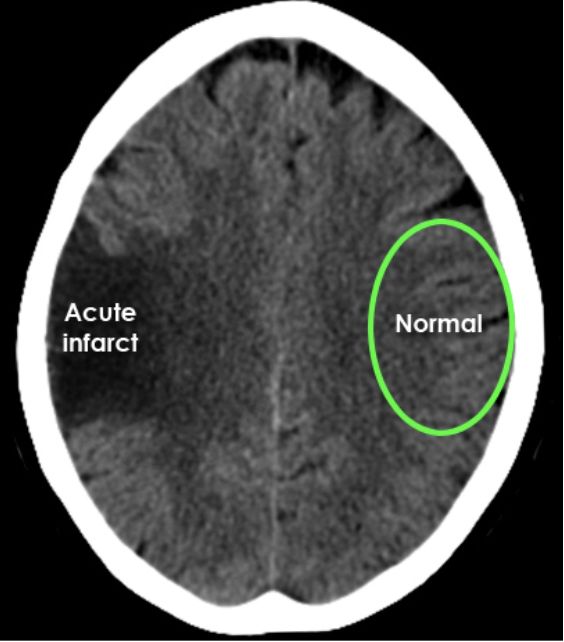

Brain CT after right-sided vessel blockage

• Now damage is visible

• Here, clear areas of irreparable brain injury can be seen on the right side, where the artery was blocked.

• At this stage, treatment options are lost—the damage is permanent.